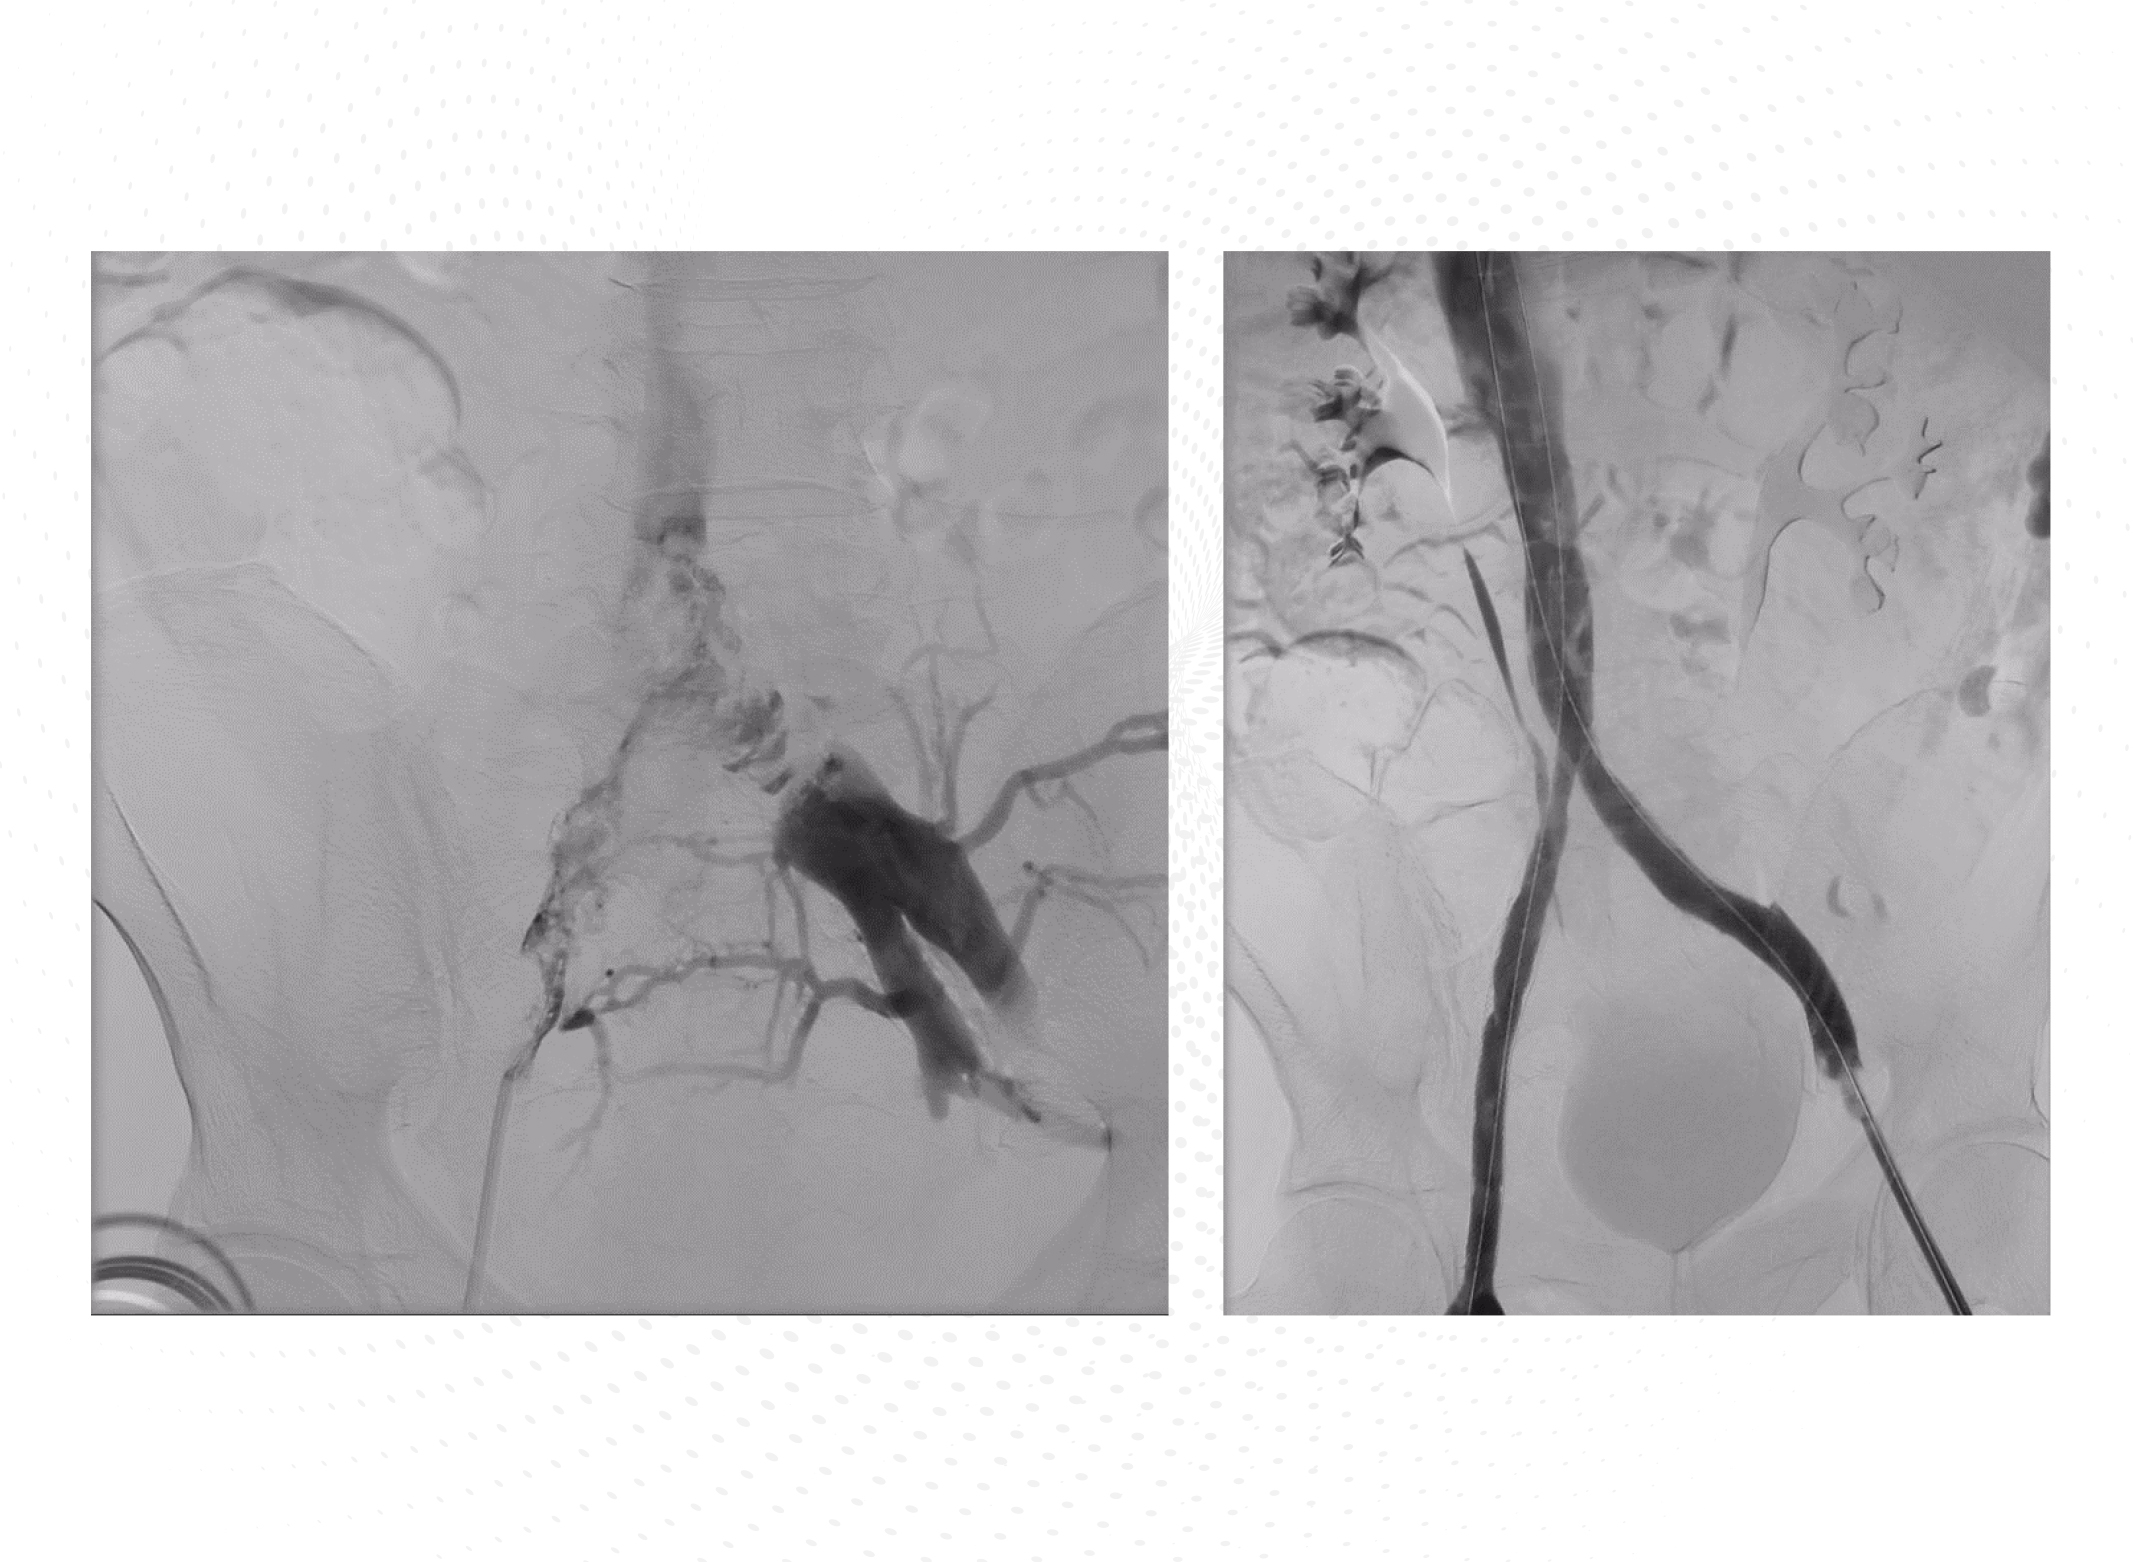

La evolución clínica inicial es satisfactoria, pero 2 meses más tarde (mayo de 2016) el paciente desarrolla edema progresivo completo de ambas extremidades inferiores. La TAC abdominal muestra progresión tumoral con crecimiento de los conglomerados adenopáticos y afectación hepática. Además, se observa trombosis en la vena cava inferior, por debajo del hilio renal derecho, en ambas venas iliacas comunes en su confluencia en la vena cava y en la vena iliaca externa derecha. Por el contrario, en la ecografía Doppler no se observaba trombosis a nivel femoral ni poplíteo (presentes en la ecografía previa de febrero). Se discute el caso entre oncología, hematología, radiología intervencionista y cirugía vascular. Con el objetivo de favorecer la mejoría sintomática, se propone la colocación de endoprótesis venosas. Periprocedimiento, se sustituye el tratamiento con HBPM por heparina no fraccionada (HNF) en perfusión intravenosa. El procedimiento transcurre sin complicaciones, con buen resultado angiográfico (Figura 2). Se constata mejoría progresiva del edema en las extremidades inferiores. A las 72 horas se sustituye la HNF por HBPM con pauta cada 12 horas, HBPM 100 mg/12 horas (por tanto, se mantiene una dosis un 20% superior a la que le correspondería por su peso).

A pesar de escalar la dosis de HBPM, el paciente había sufrido una nueva recurrencia trombótica, afectando venas iliacas y cava inferior (en muy probable relación con compresión extrínseca por masa tumoral). Dada la complejidad del caso, se discutió el mismo entre los diferentes departamentos implicados. Se desestimó fibrinolisis farmacológica por el riesgo hemorrágico y por el tiempo transcurrido desde el inicio de los síntomas hasta que acudió a valoración, lo que reducía la probabilidad de éxito. La afectación trombótica de la vena cava a nivel infrarrenal dificultaba técnicamente la inserción de un filtro, pero sobre todo había temor a las consecuencias de una trombosis completa de la vena asociada al filtro. El paciente no tenía contraindicación para la anticoagulación. Finalmente, se optó por colocación de endoprótesis venosas y modificar la pauta de HBPM a una posología cada 12 horas, continuando en un escalón supraterapéutico.